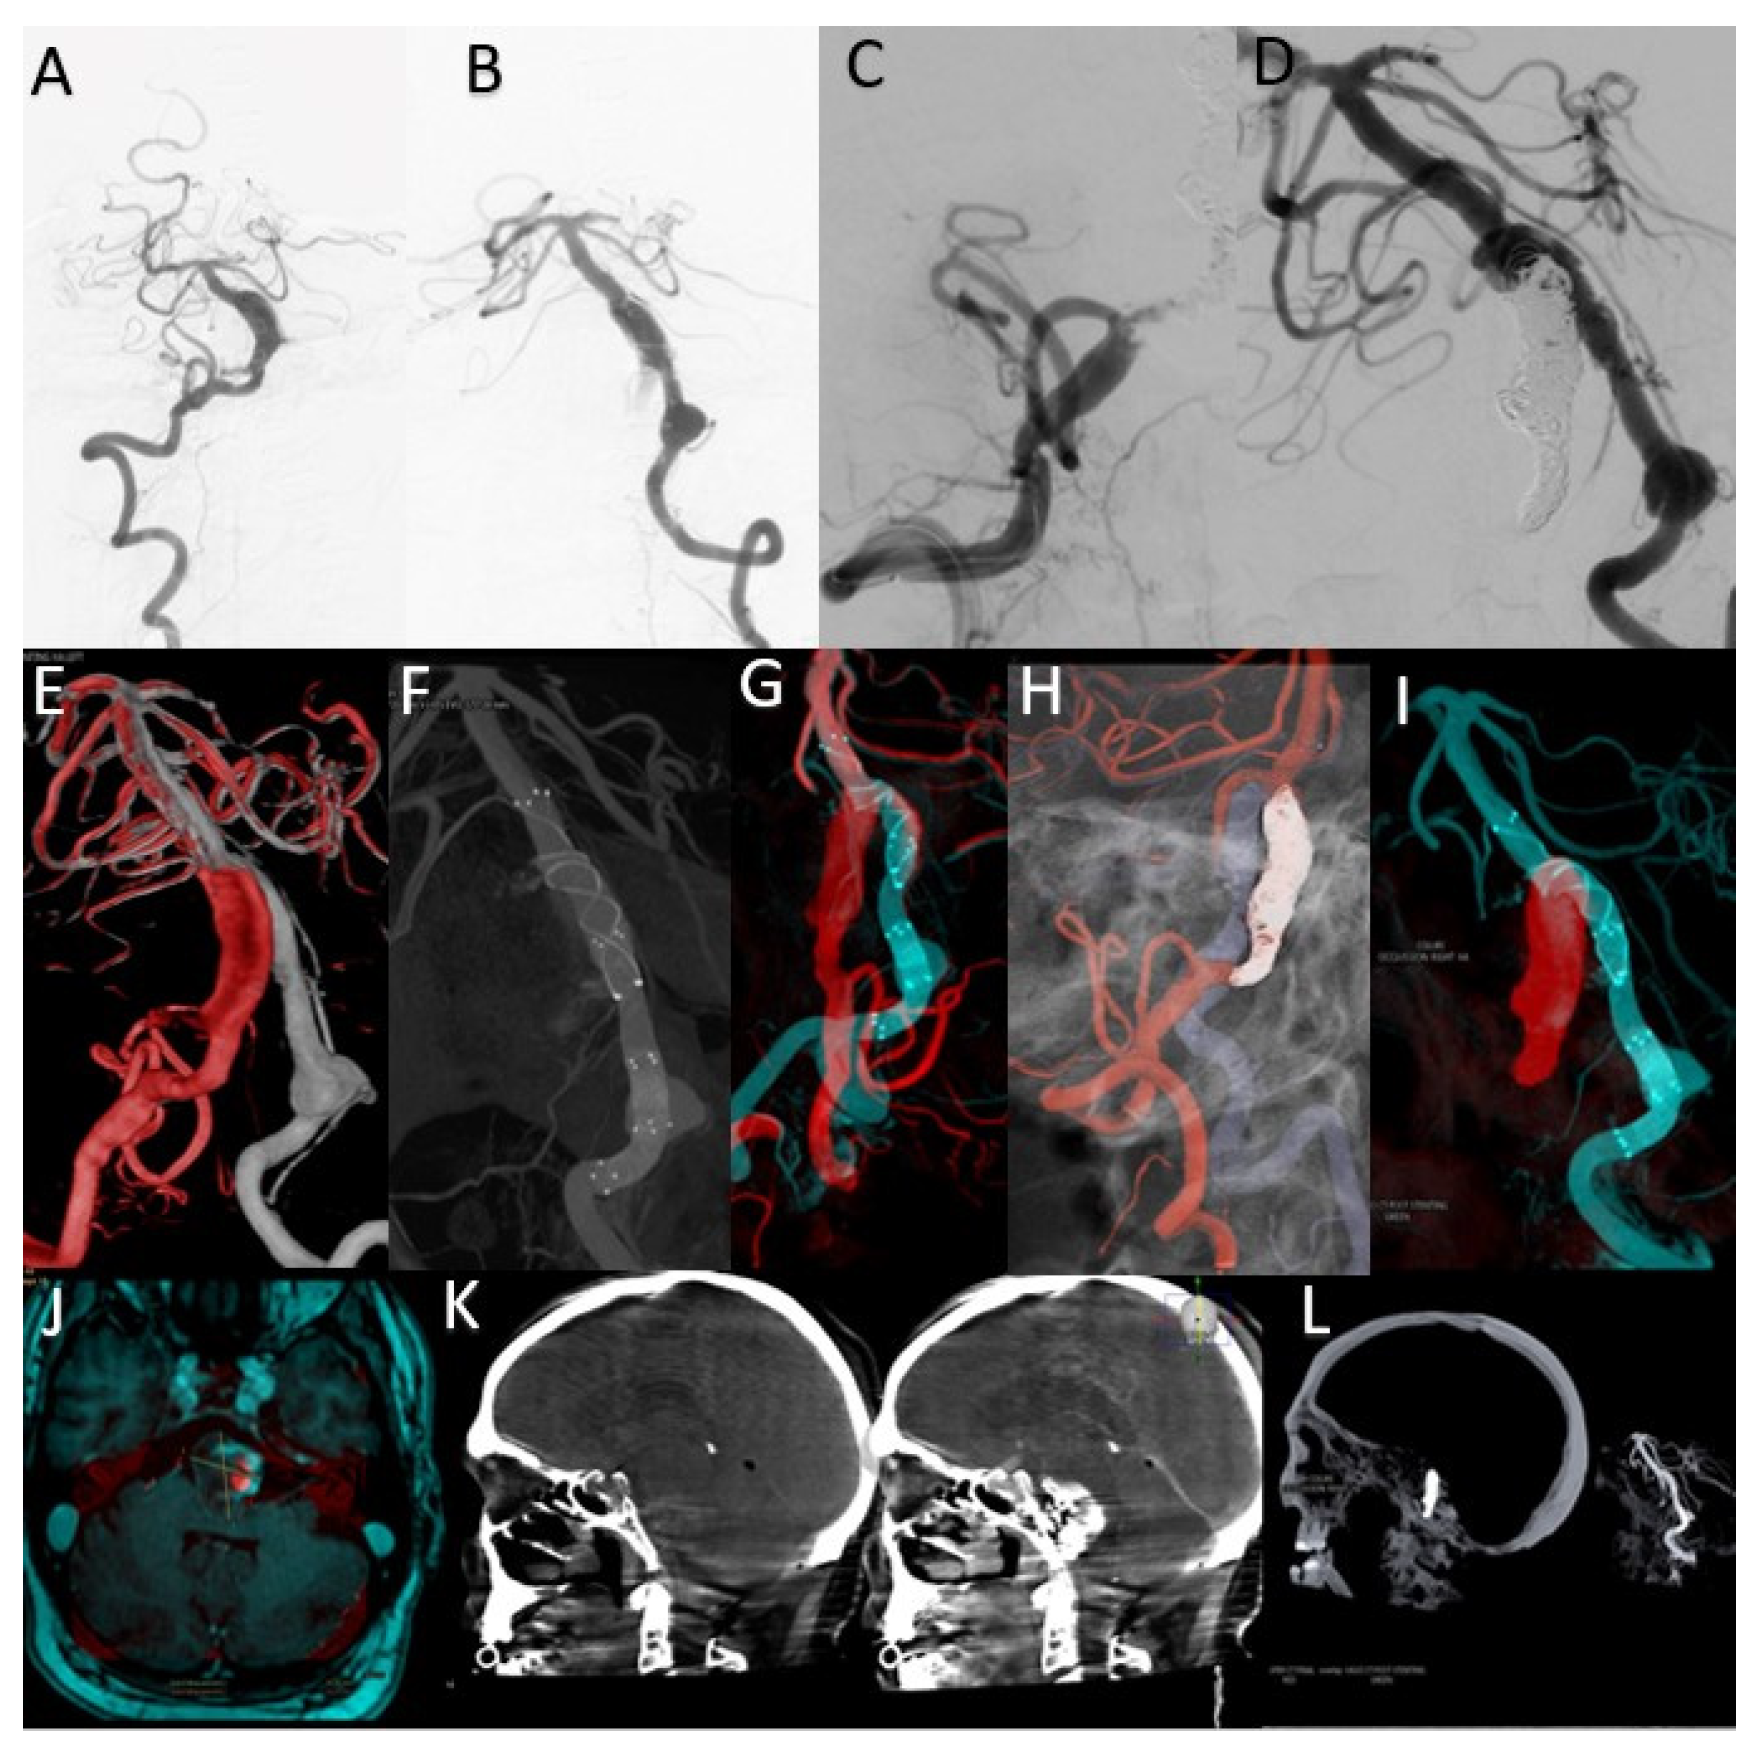

This case concerns a 43-year-old patient who presented to the emergency room for dysarthria and gait disturbances. He was diagnosed after imaging investigations with a fusiform aneurysm of the vertebrobasilar junction (Figure 6A,B).

Figure 6.

(A) Right VA preoperative DSA. (B) Left VA preoperative DSA. (C) Right VA postoperative DSA. (D) Left VA postoperative DSA. (E) Overlay between the right VA 3DRA (red) and left VA 3DRA (grey). (F) Left VA VasoCT MIP after stents deployment. (G) MIP Overlay between right VA 3DRA (red) and right VA VasoCT (blue) after stents deployment. (H) 3D Roadmap overlay between right VA 3DRA (red) and left VA 3DRA (grey) during the right VA distal segment occlusion. (I) MIP Overlay between the right VA coiled segment 3DRA (red) and right VA VasoCT (blue). (J) Overlay between the 1-month control MRI and left VA VasoCT at the end of the treatment. (K) Overlay between the XperCT preoperative sagittal volume and the XperCT postoperative sagittal volume. (L) Overlay between the XperCT postoperative sagittal volume and the pre-operative left VA 3DRA volume.

The overlay between the two 3DRA volumes obtained by injection into the left and right vertebral arteries helped determine the best therapeutic strategy as stenting one vascular axis and sacrificing the other axis (Figure 6E). After analyzing the aneurysmal morphology and the vessels involved, it was decided to stent the left vertebrobasilar axis and occlude the final portion of the right vertebral artery.

By comparative analysis of the normal anatomy, we notice that the left PICA artery has its origin in the inferior portion of the aneurysmal sac while the right PICA artery has its origin at a distance from this aneurysm. Given these elements, the decision was made to preserve the right PICA by segmental closure of the vertebral artery between the stents placed on the right vertebrobasilar axis and the emergence of the artery (Figure 6C,D,I).

Moreover, the overlay of the 3DRA volume of the left vertebrobasilar axis with the VasoCT examination of the same axis, performed after telescopic placement of three stents (Figure 6F,G), helped to appreciate the areas of overlay between the distal and middle stent and also between the middle and proximal stent. As during MRI follow-up, a dimensional increase was observed (Figure 6J), and it was decided to place a new flow-diverter stent inside the first stent, with the purpose of covering the aneurysmal neck.

The sagittal XperCT volume pre-operative displayed near the sagittal XperCT volume post-operative, overlayed, but in mirror (independent function of Overlay XtraVision software), as in Figure 6K, provides information regarding potential bleeding from the giant basilar aneurysm in the posterior fossa, and can assess the mass effect and its relation with the posterior fossa craniectomy in such complex cases.

The analysis of these overlaying volumes is very useful as a result of the need for the subsequent placement of a FlowDiverter stent to cover the area of the dysplastic aneurysmal neck at the vertebrobasilar junction, as the segment with the active thrombus continues to recruit despite the initial placement of platinum coils inside the aneurysmal sac.